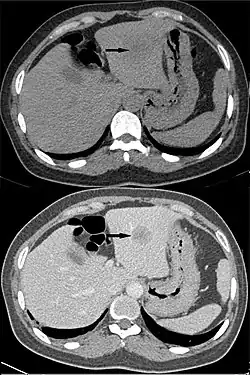

Hepatocellular carcinoma, without (top) and with (bottom) IV contrast

"Washout" is where tissue loads radiocontrast during arterial phase, but then returns to a rather hypodense state in venous or later phases. This is a property of for example hepatocellular carcinoma as compared to the rest of the liver parenchyma.[3]